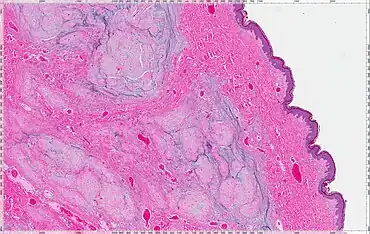

| Cutaneous myxoma or Superficial angiomyxoma | Poor to moderately circumscribed, multilobular | Scattered thin-walled vessels | Moderately cellular, bland spindled and stellate cells, variable inflammatory cell infiltrate | Abundant mucin with clefts. Up to 30% have an associated epithelial component | Vimentin; variable staining with CD34, factor XIIIA, SMA1, MSA2 and S-100 | 20–30% | ![]() |